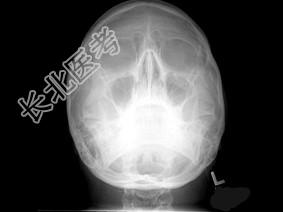

- 多项选择题女,25岁, 车祸伤及面部,X线及CT检查如图所示, 正确的描述或诊断是 ( )

A、X线示左侧眶底较正常变低

C、左侧上颌窦内见气-液面

D、左侧眶底骨折

E、左侧上颌窦积液